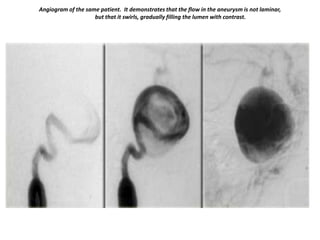

Angiogram of the same patient. It demonstrates that the flow in the aneurysm is not laminar,

but that it swirls, gradually filling the lumen with contrast.